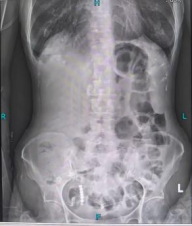

林奶奶的身体早已被病痛反复透支:4年前,她因子宫平滑肌肉瘤接受了一场大手术,术后虚弱不堪,无法承受后续化疗,只能靠定期复查勉强维持。原以为能平稳度日,没想到1个月前,无明显诱因的全腹胀痛突然袭来。随着时间推移,疼痛越来越剧烈,还伴着恶心、无法进食,最终完全停止排气排便。这让本就虚弱的林奶奶焦虑不已,担心自己扛不住新一轮手术治疗。

根据林奶奶的情况,团队最终确定林奶奶的“救命招”——病房床旁胃镜下肠梗阻导管置入术,这也是针对重症梗阻患者的特色技术。考虑到林奶奶疼痛难忍、无法移动,叶晋生团队在床旁不到10分钟便完成了肠梗阻导管植入术,随着大量的肠液被引出,林奶奶的腹胀腹痛症状得到了有效缓解。

这根长达280cm的特殊导管,比普通胃管更长、更精准,能借助胃肠蠕动直达梗阻部位,实现充分减压——不仅快速缓解了肠梗阻带来的腹胀腹痛,为后续手术创造安全条件。与此同时,团队同步给予静脉肠外营养支持,确保林奶奶在术前维持良好的营养状态,为手术耐受打下基础。

导管置入后,林奶奶的症状明显缓解,叶晋生通过进一步检查发现,林奶奶的肠梗阻并非单纯粘连所致,而是盆腔占位压迫肠道,考虑为子宫平滑肌肉瘤复发,且已侵犯直肠及膀胱,必须通过手术切除病灶才能从根源解决问题。叶晋生第一时间启动多学科会诊,麻醉科、ICU、消化科、肿瘤科等科室专家,共同评估病情及围手术期风险,

核心优势:长度达280cm,能直达梗阻部位,减压效果远超普通胃管;

便捷性:可在病房床旁操作,10分钟内完成,无需往返胃肠镜室,适合疼痛难忍、无法移动的患者;

双重作用:快速缓解腹痛腹胀,同时扩张肠管,为手术创造更安全的条件,降低穿孔风险;